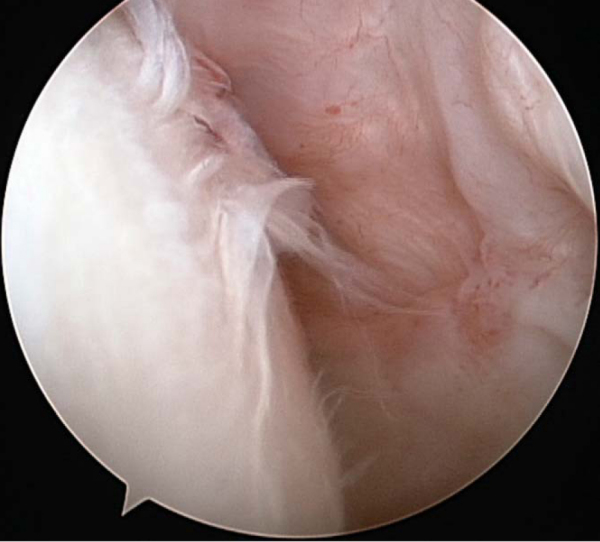

Arthroscopic débridement permits evaluation of the humeral and glenoid joint surfaces, removal of chondral loose bodies, and synovectomy when indicated. Selective capsular release, in the authors’ opinion, should always precede more significant operative treatment (

Fig. 30-2

).

Figure 30-2 at the time of diagnostic arthroscopy and débridement, demonstrating grade III-IV changes across the humeral head as well as glenohumeral synovitis. |